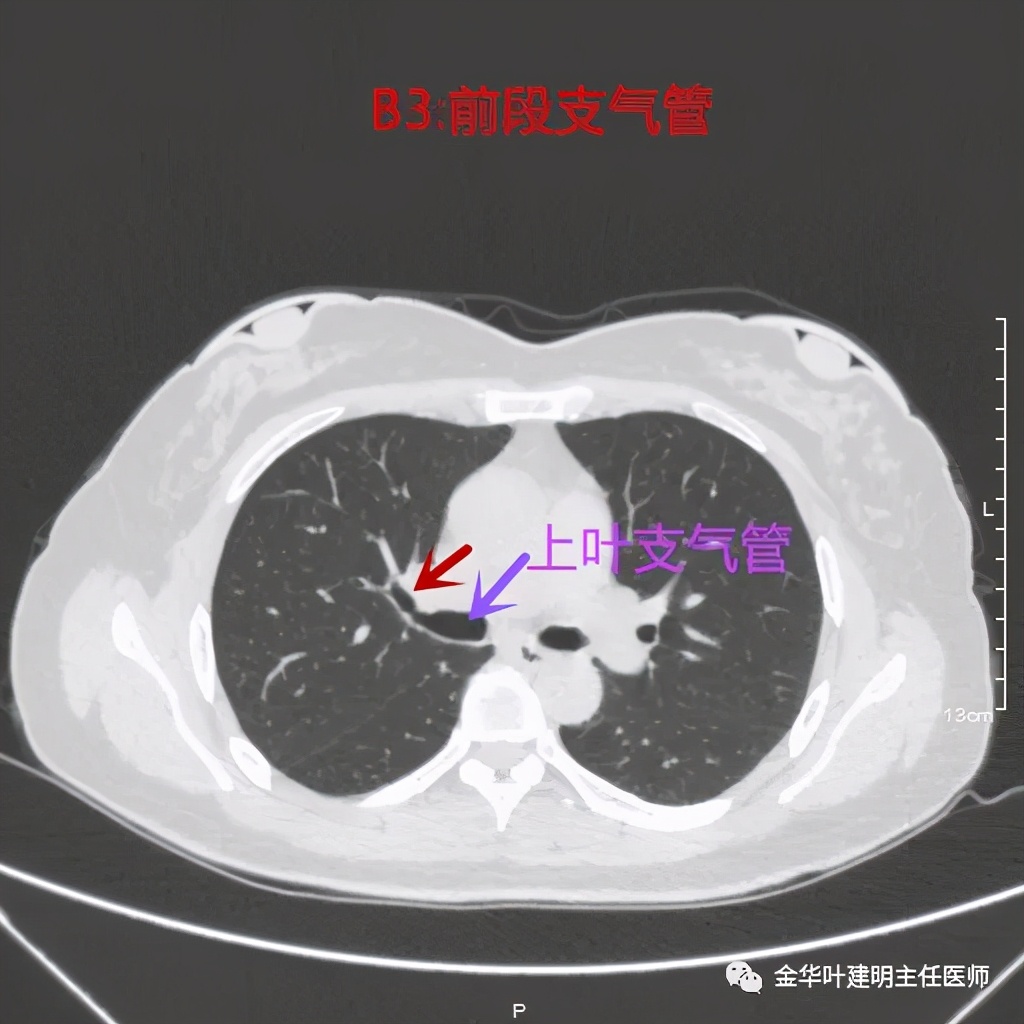

前段:本例前段显示比较清楚,图片较少,我们直接上图:

紫色所指是上叶支气管,红色示前段支气管

上两图示前段的外亚段与内亚段支气管,显示了分叉处